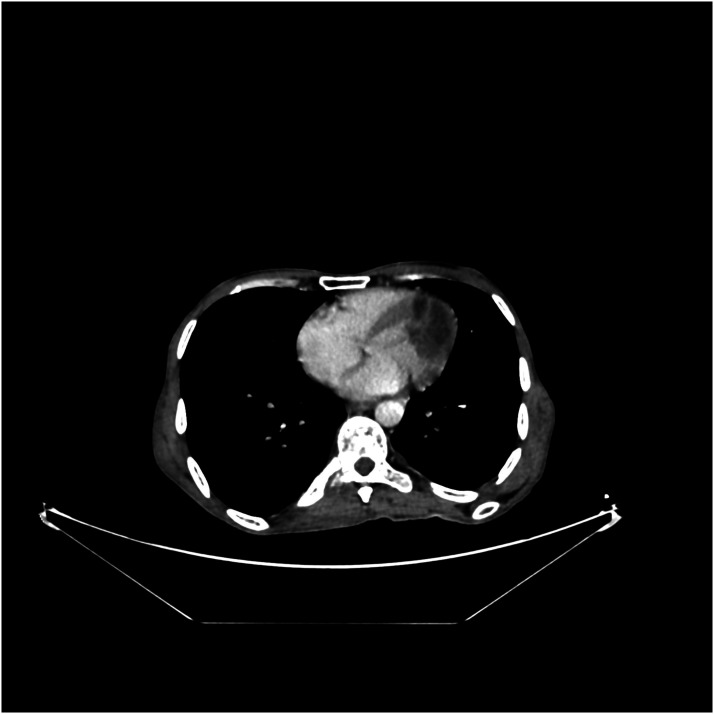

Cardiac metastases are the most frequent cardiac tumors. They can cause dysrhythmia, myocardial dysfunction, pericardial effusion, and heart failure. In decreasing order, the major primary malignancies associated with cardiac metastases are pleural mesothelioma, lung adenocarcinoma, undifferentiated carcinomas, lung squamous cell carcinoma, and breast carcinoma. Cardiac metastasis of sarcomas is uncommon, and only a limited number of cases have been found in literature. We report the case of an incidentally discovered cardiac metastasis when assessing the extension of a thigh mass in a 45-year-old man.

Abstract Image